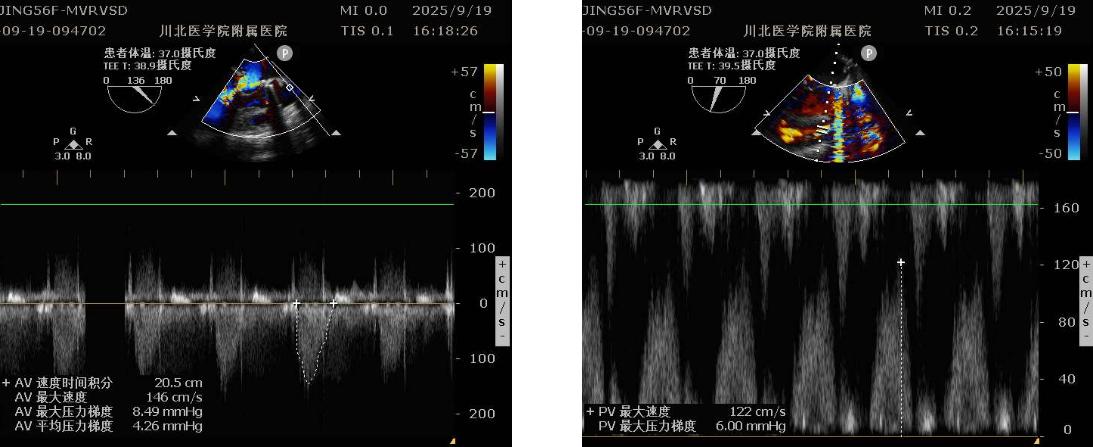

该患者为56岁中年女性,因反复胸闷胸痛、气促10+年,加重1月,2025819日到我院心血管内科住院治疗。入院后完善检查,提示:1.风湿性心脏病:二尖瓣中度狭窄伴重度关闭不全、主动脉瓣重度狭窄伴重度关闭不全、三尖瓣中度关闭不全;2.先天性心脏病:室间隔缺损、右室流出道狭窄;3.左心房及左心室显著扩大(左房舒末前后径:65mm,左房收末前后径54mm,心电图提示心房颤动,血液检验结果提示肝功能及胆红素明显升高,考虑肝淤血。为求进一步治疗,患者于829日转入心脏大血管外科,给予积极抗心衰、营养支持等治疗919心脏大血管外科主任赖应龙带领向军博士、彭泰峦医生等人在手术中心主任涂发平及医护团队配合下成功为患者实施了八种手术,术后患者安全返回心脏大血管外科重症监护室。术毕食道超声提示:二尖瓣仅残留少量关闭不全外,其余所有心脏问题全部解决,心律转为窦性心律。患者于术后2小时苏醒,成功撤离呼吸机,于术后10小时开始进食,目前已下床活动。

术前二尖瓣、主动脉瓣情况

术后主动脉瓣、二尖瓣情况